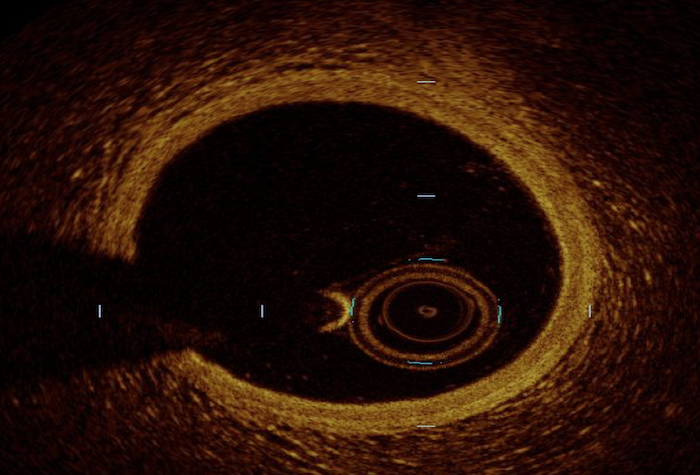

| Image acquisition (normal coronary vessel anatomy shown): | ![]() |

![]() |

The differences in penetration and resolution explain the inherent limitations

of both modalities in comparison. Given its relative limited resolution, IVUS is

unable to evaluate the separation of the vessel wall layers (i.e., intima, media

and adventitia) compared to OCT [10]. Therefore, OCT is better served within

reasonable penetration (

Lastly, irrespective of considerations on penetration and resolution, the need for a bloodless field by high velocity contrast injection with OCT carries two pertinent limitations. First, the identification of aorto-ostial lesions is limited by such a need with OCT, and second, the use of OCT requires the use of contrast and inherently carries a risk of contrast induced nephropathy, particularly for patients with renal impairment [8]. Considering these parameters, the safety and feasibility of both modalities have been shown to be comparable in observational studies [19, 20].